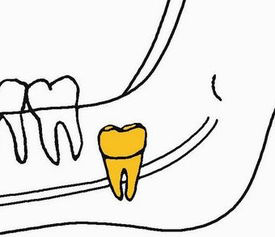

或发育完成,但位置合适

就可以把它留下来